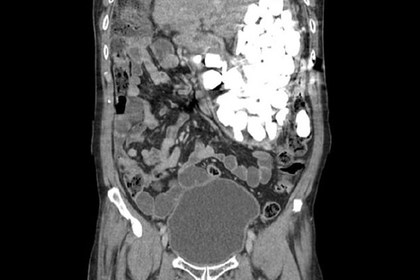

Из желудка жителя южнокорейского города Коян извлекли около двух килограммов камней, крышек от бутылок и монет. Об этом сообщает издание Daily Mail.

54-летний мужчина обратился к врачу с жалобой на боль в животе. Его живот был раздут, а при пальпации под кожей ощущались объекты, напоминающие мелкие камни. Пациент признался, что часто глотает монеты и гравий, чтобы успокоиться.

Рентген показал, что его желудок полностью заполнен инородными телами. Первоначально проглоченные предметы планировали извлечь при помощи гастроскопа, однако их оказалось слишком много. Чтобы вынуть камни, бутылочные крышки и монеты, понадобилась хирургическая операция. Мужчина провел в больнице девять дней.